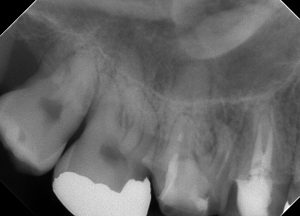

レントゲンを見てみよう。

(術前レントゲン、CT)

全ての根管に、根尖病変が存在する。

打診(+)、咬合痛(+)の状態であった。